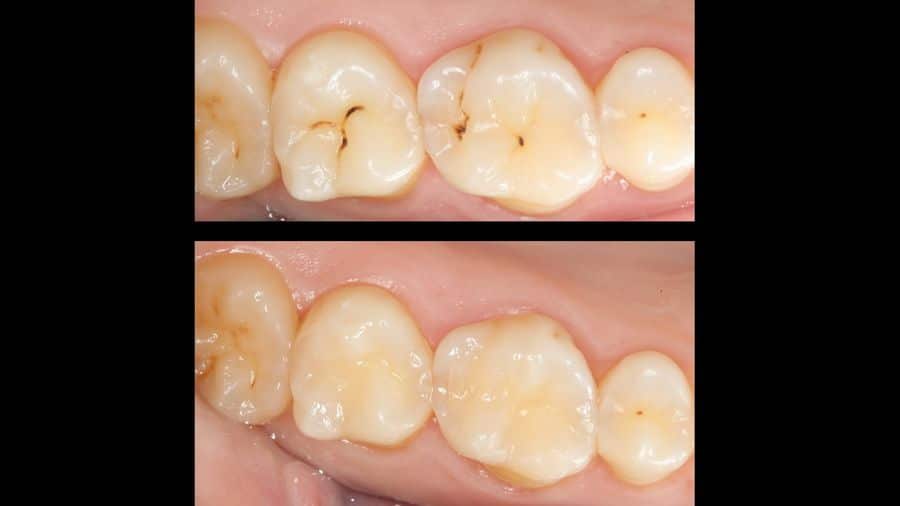

Air abrasion. Minimally invasive tooth decay treatment

Dental air abrasion is a minimally invasive method of treating caries, with no discomfort, vibrations or high-pitched sounds

The air abrasion treatment system consists of using a spray of 30 – 80 micron aluminium oxide particles to eliminate the caries tissue without the need for a burr (the classic drill with the high-pitched sound). The instrument does not touch the tooth, only the spray does, and so the vibration is barely noticeable.

Furthermore, the use of air abrasion means we can cure even extremely small caries. It is a minimally invasive method for treating caries. The combination of early detection (DIAGNOdent, radiovisiography, endoscopy, etc.) with minimally invasive caries treatment improves and simplifies the maintenance of dental health. In this manner we can cure caries with minimal repair work, maintaining the maximum amount of healthy tooth as possible, with no need for anaesthesia, with no discomfort, in a short time, inexpensively and with a better long-term outcome.